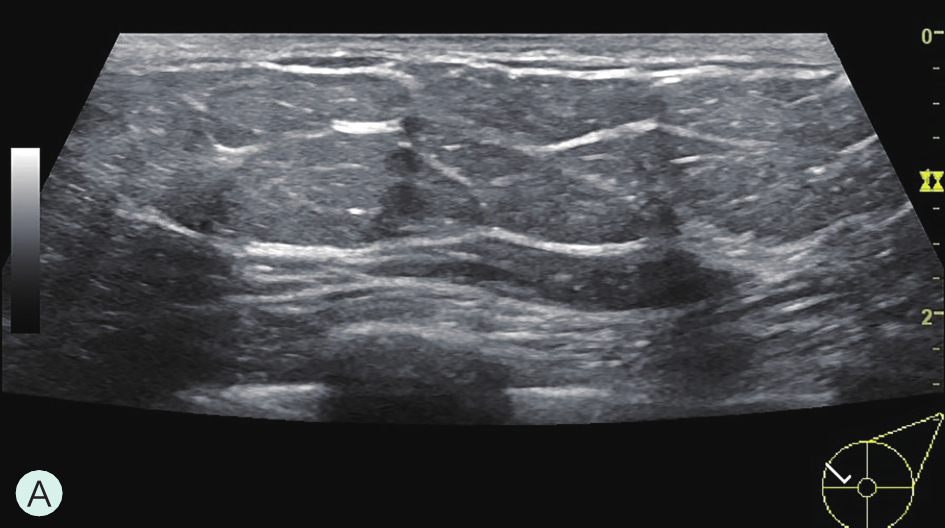

图1-3-2 乳腺超声不同乳腺密度

A.脂肪型;B.散在致密型;C.不均匀致密型;D.极度致密型